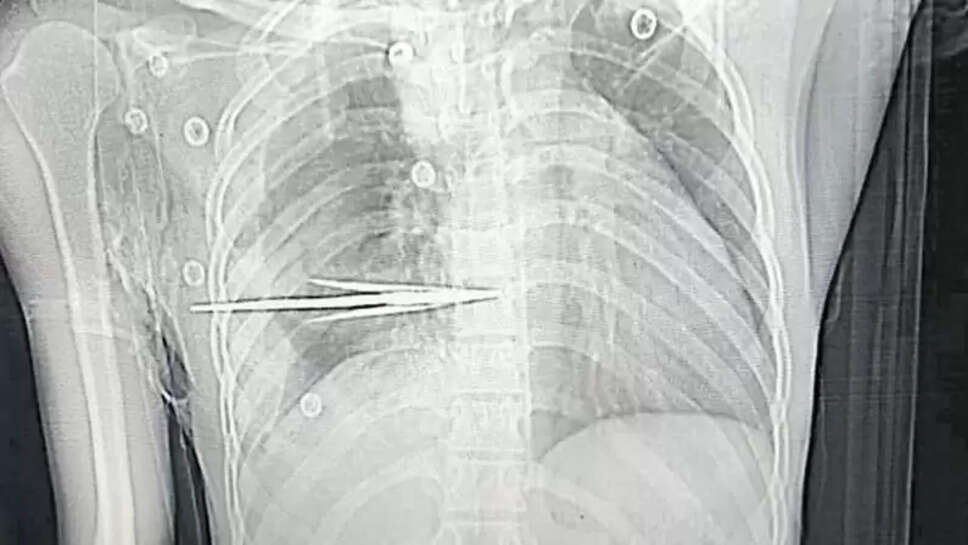

முதலுதவி சிகிச்சைக்கு பிறகு தெலுங்கானா மாநிலம் வாரங்கல் எம்ஜிஎம் மருத்துவமனைக்கு கொண்டு செல்லப்பட்டு, அங்கிருந்து மேல் சிகிச்சைக்காக ஹைதராபாத் நிம்ஸ் மருத்துவமனைக்கு கொண்டு சென்றனர். அங்கு டாக்டர்கள் சிடி ஸ்கேன் எடுத்து பார்த்தபோது இதயத்துக்கு மிக அருகில் நுரையீரலின் பக்கவாட்டு பகுதியில் அம்பு உடைந்திருந்தது உறுதியானது.

சுமார் 3 மணி நேர அறுவை சிகிச்சைக்கு பிறகு நிம்ஸ் மருத்துவர்கள் அம்பை பத்திரமாக அகற்றி சிறுவனின் உயிரை காப்பாற்றினர். அம்பு எறிந்து ரத்தம் வழிந்த நிலையில், மருத்துவர்களின் துரித நடவடிக்கையால் சிறுவனின் உயிர் காப்பாற்றப்பட்டது. இந்த பணியை வெற்றிகரமாக முடித்த டாக்டர் அமரேஸ்வர ராவ் மற்றும் டாக்டர் பீரப்பா ஆகியோரின் நிம்ஸ் குழுவிற்கு பலரும் வாழ்த்து தெரிவித்து வருகின்றனர்.